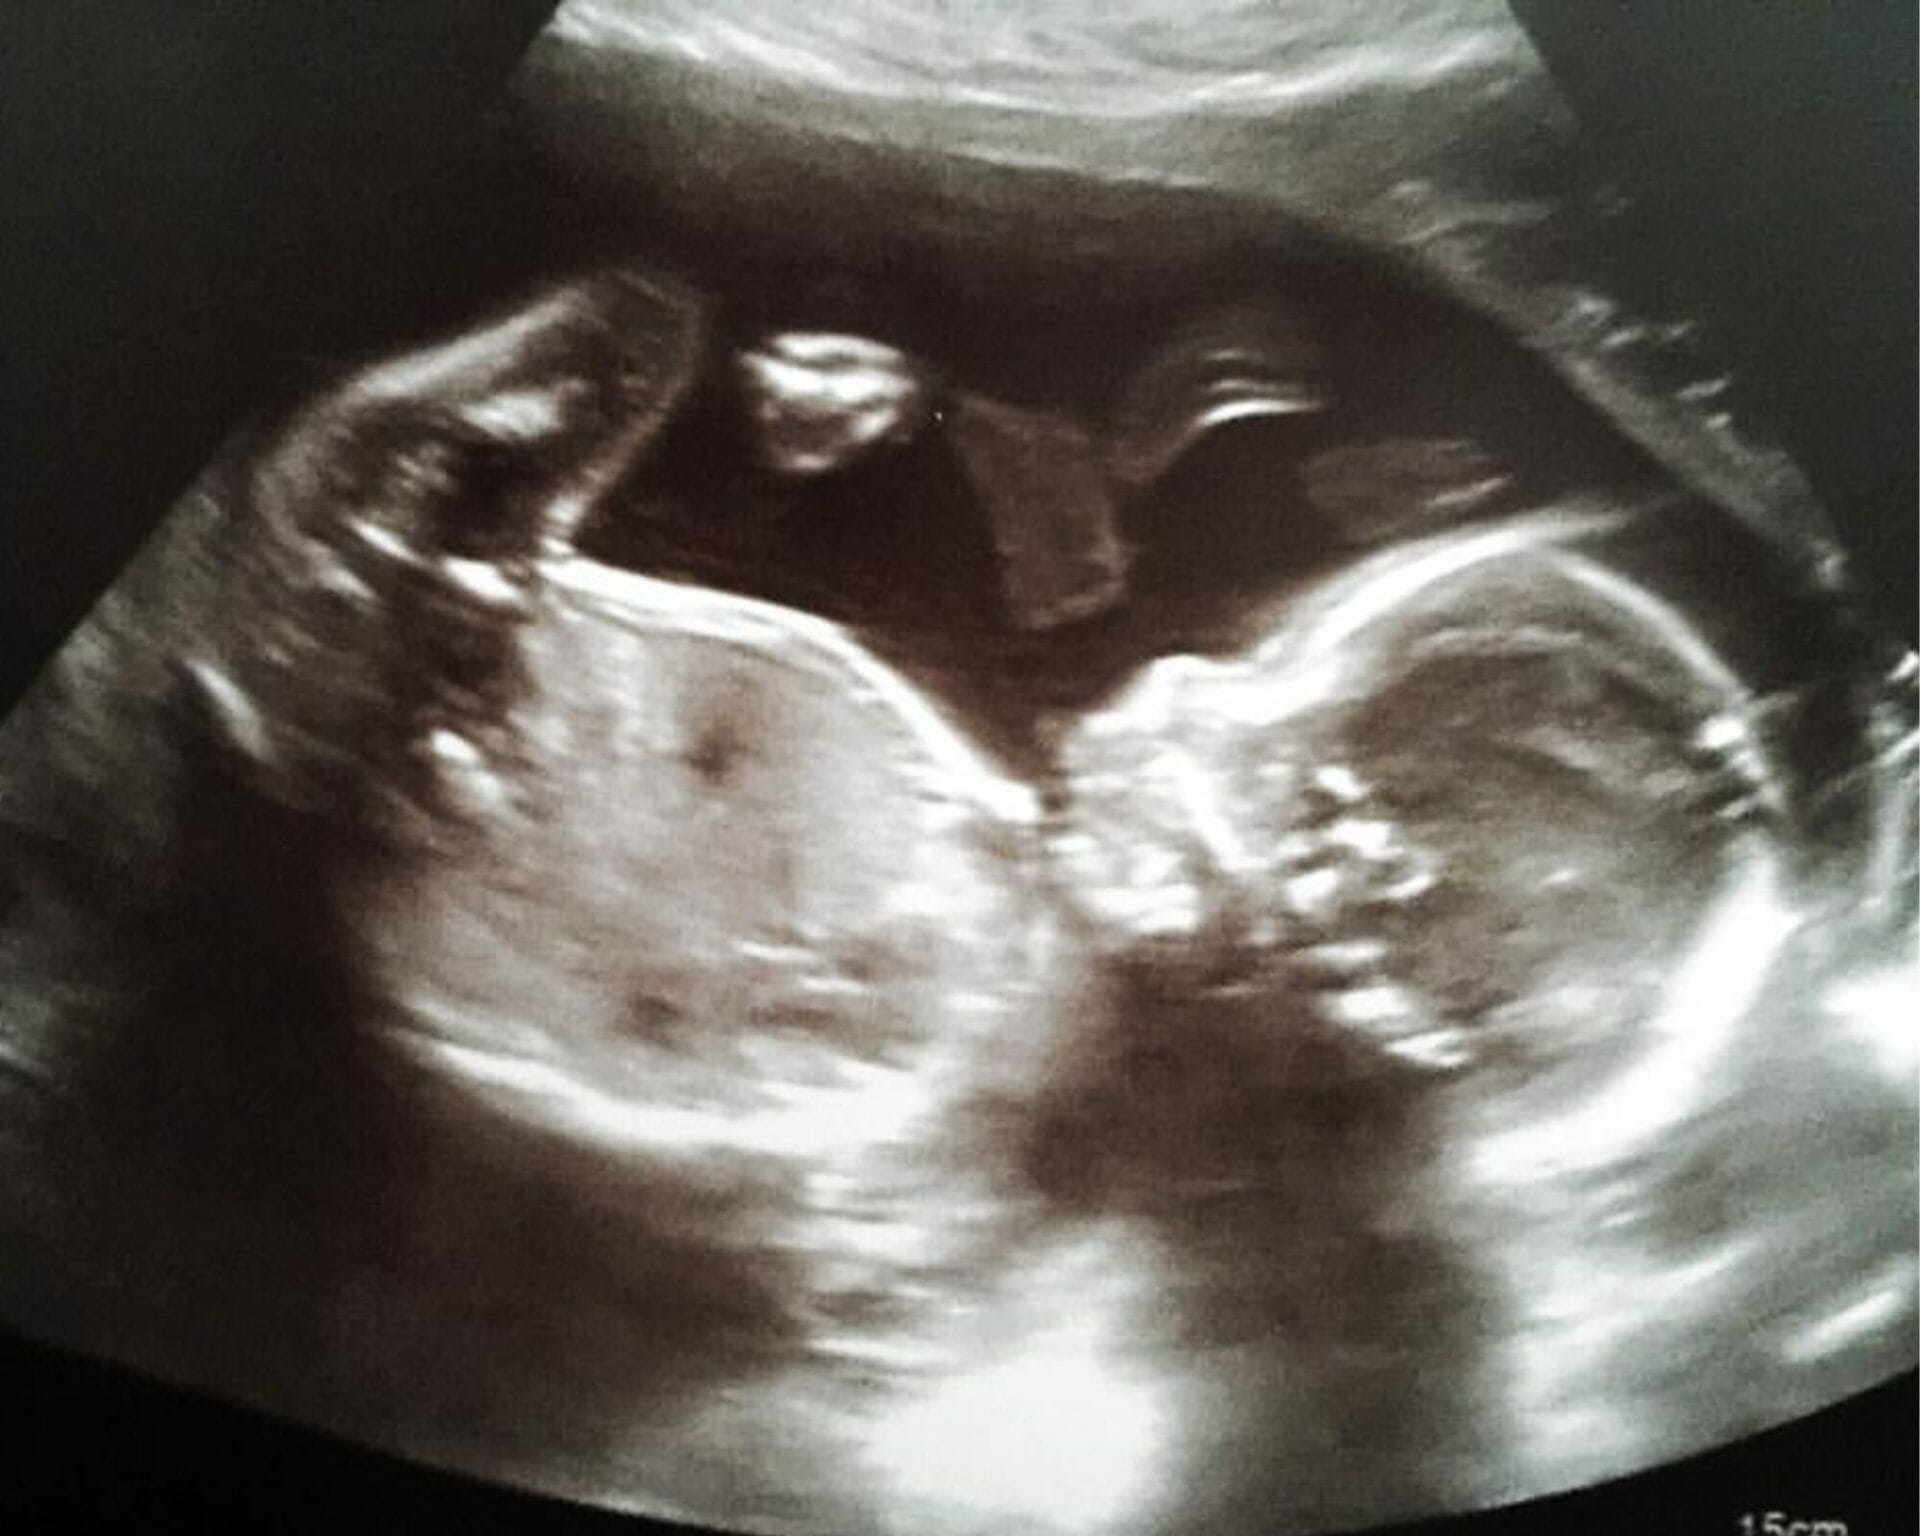

عند ذهابك الى الطبيبة سيتم قياس طفلك للتأكد من أن نموه يسير على الطريق الصحيح، وسيتم فحص الأجهزة الرئيسية المناسبة مثل قياسات الجنين في الرأس والبطن وعظم الفخذ، رأس الجنين والصدر والبطن، وجه الجنين، والعمود الفقري الجنيني وفحص الأطراف، وسيتم فحص السائل الأمنيوسي وموقع المشيمة ومعدل ضربات قلب الجنين للتأكد من صحة الطفل، وسوف يُظهر الفحص أيضًا موضع المشيمة في الرحم والمناطق المحيطة بها مثل الأورام الليفية، أو أكياس المبيض وعنق الرحم المغلق

قد يتم في بعض الأحيان التعرف على المشيمة النازلة (حيث يتم ربطها بالجزء السفلي من الرحم) عند الفحص لا تقلقي كثيرًا كما هو الحال في 90 % من الحالات بينما ينمو طفلك، يسحب رحمك الموسع بشكل طبيعي المشيمة لأعلى بعيدًا عن عنق الرحم بالنسبة لبعض النساء لا تزال المشيمة تقع في الجزء السفلي من الرحم بعد 20 أسبوعًا.

إذا كانت المشيمة تمنع فتح الرحم جزئيًا أو كليًا في نهاية فترة الحمل فإن هذا يُعرف باسم” المشيمة البريفيا ” .

هذا يؤثر على 1 من كل 200 ولادة ومع ذلك إذا ثبت أن المشيمة تغطي عنق الرحم عند إجراء الفحص فسيتم تقديم مسح آخر بين 32 إلى 36 أسبوعًا للتحقق من انتقاله.